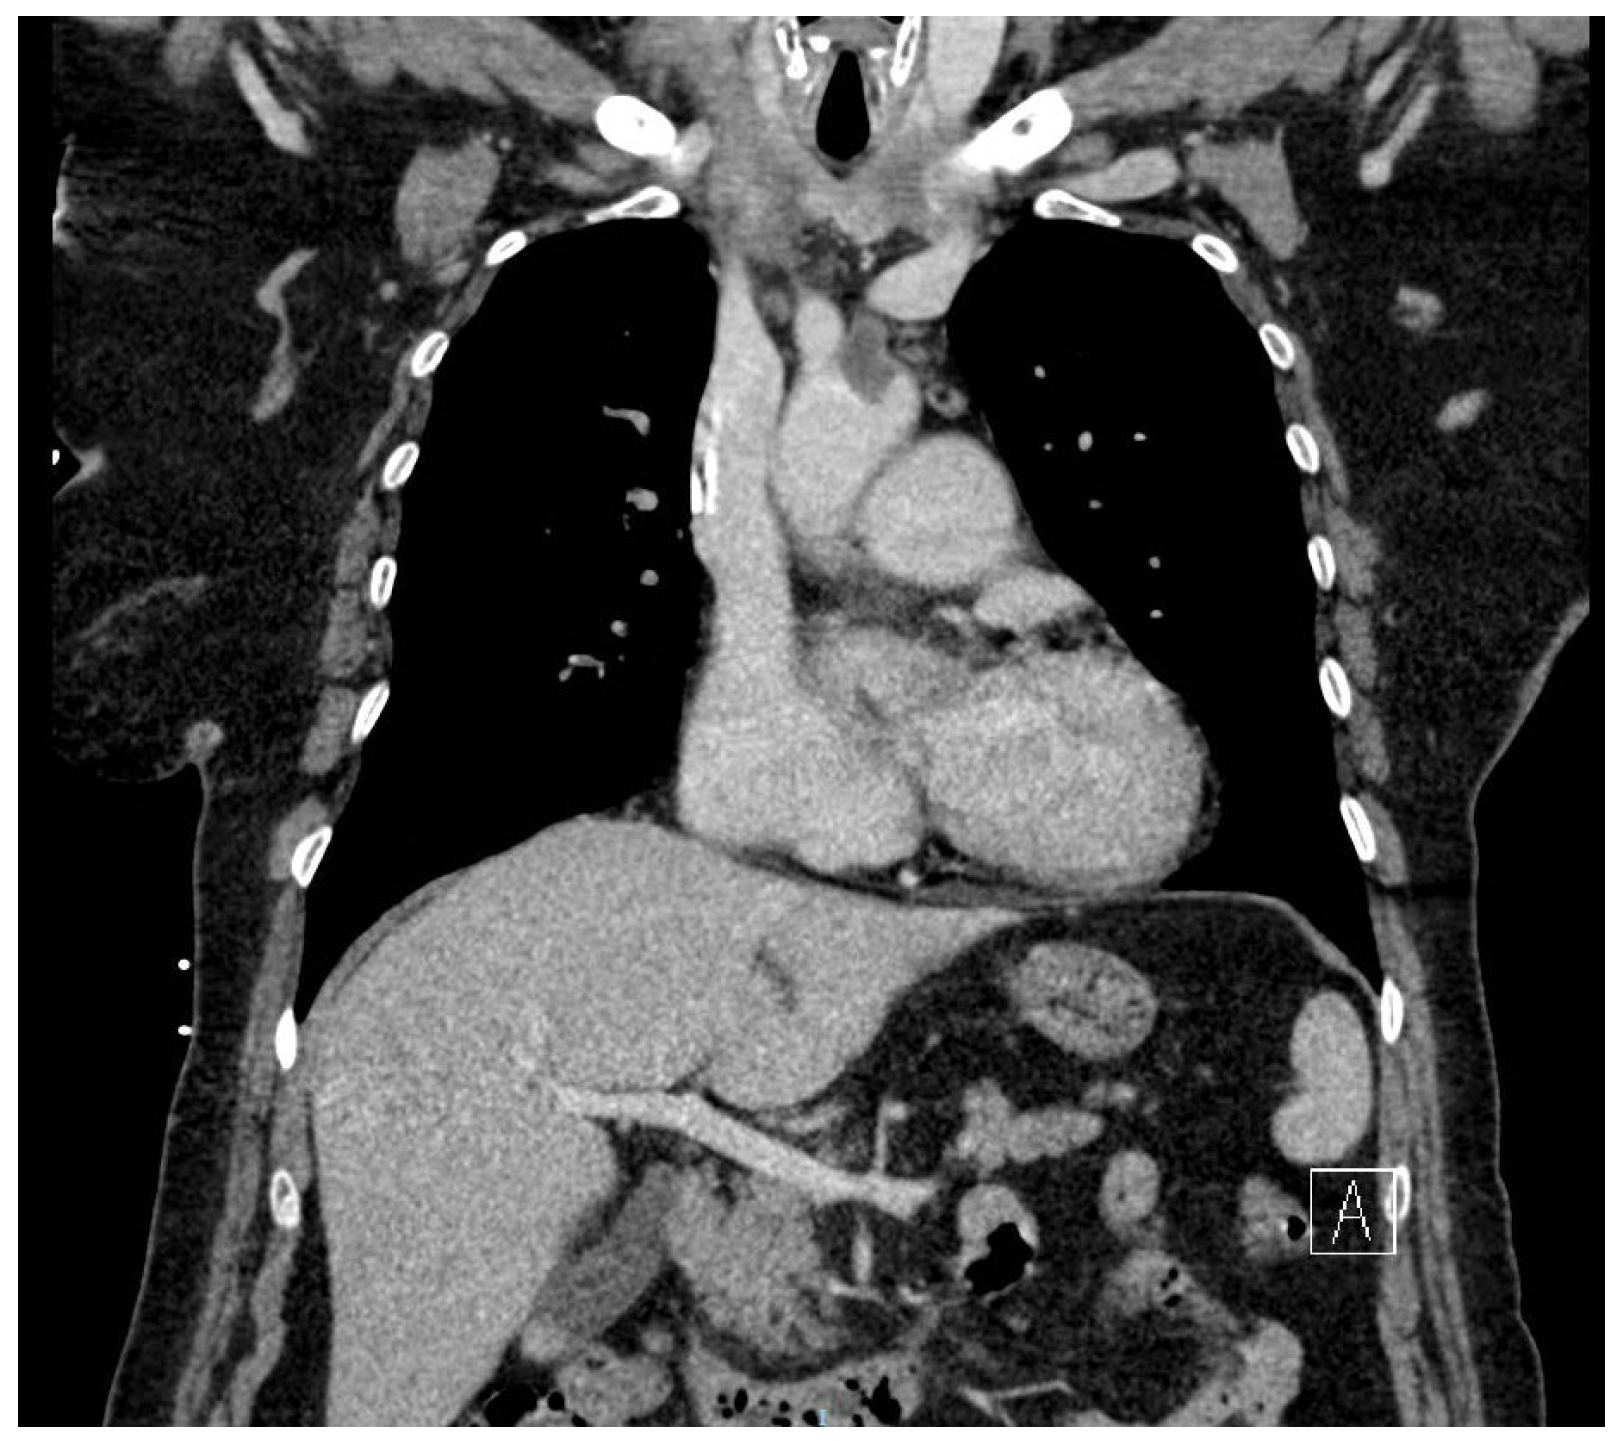

Rare Case of Grade 3 Undifferentiated Pleomorphic Sarcoma in Left Atrium, Mitral Valve, and Papillary Muscle

2. Case Report